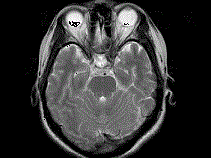

问题 女,41岁,阵发性头痛伴恶心、呕吐20余天.CT影像如图,最可能的诊断为 ( )

选项 A、双侧筛窦息真菌感染 B、双侧筛窦过敏性炎症 C、双侧筛窦炎 D、双侧筛窦未见明显异常 E、双侧筛窦息肉

答案 C